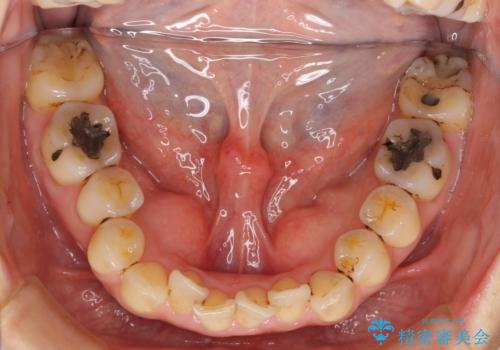

前歯のガタガタ 治療期間がかかっても良いので非抜歯でマウスピースで

- 前歯のガタガタを主訴に来院。

前歯は開咬傾向であり、小臼歯から大臼歯にかけてもオーバージェットは非常に小さく咬耗していました。

非抜歯で前歯の重なりを作るのは難しいとご説明しましたが、インビザラインでできるところまで並べていくことになりました。